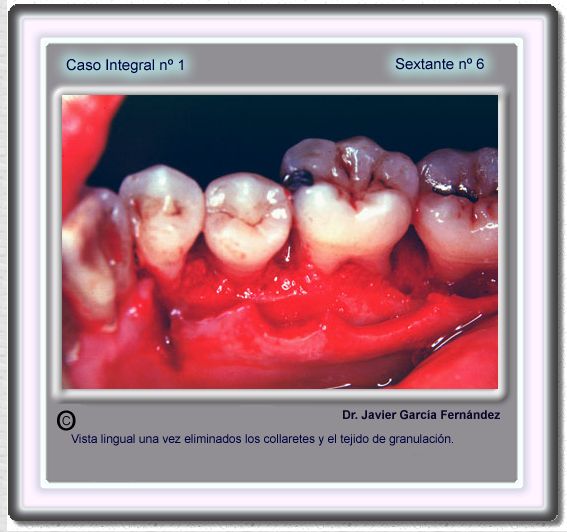

image 105